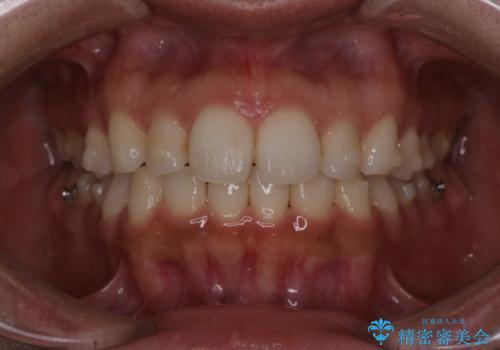

【インビザライン】前歯の後戻りを再矯正

- 前歯が出ていることを主訴に来院されました。検査の結果、口元が標準より出ているわけではなかったため今回はIPRと拡大をし、非抜歯で治療を行いました。

非抜歯でも歯軸の向きを改善したことで前歯が下がり、出っ歯に見えてしまうという主訴が改善しました。